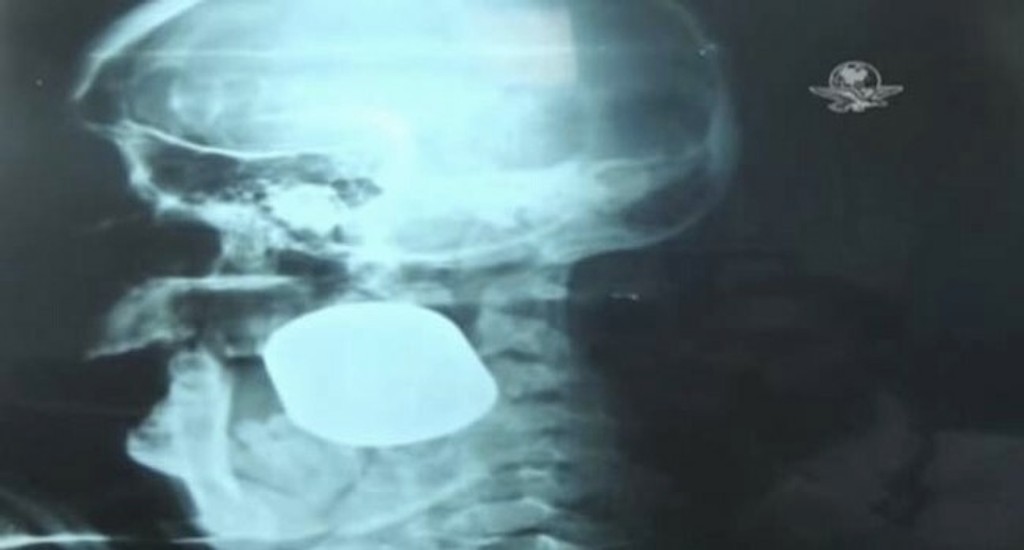

Okoloidúci muž zobral matku troch detí v bezvedomí do nemocnice. Lekári po jej príchode zostali zhrození. Karola mala v pravej časti tváre uviaznutý nebezpečný predmet.

Vojenskí lekári predmet identifikovali ako granát vystrelený z granátometu. Granát bol stále funkčný a mohol vybuchnúť. Pri nesprávnej manipulácii by tak mohol zrovnať so zemou všetko do dosahu 32 metrov.

Lekári a odborníci na výbušniny našťastie pacientku izolovali a po dlhej a náročnej operácii jej nebezpečný predmet z tváre vytiahli. Aj keď sa Karolu podarilo zachrániť, žena má pred sebou ešte dlhú cestu liečby.

Okrem veľkej jazvy na tvári totiž stratila aj polovicu zubov. Lekári predpokladajú, že rekonvalescencia by mala trvať tri roky.